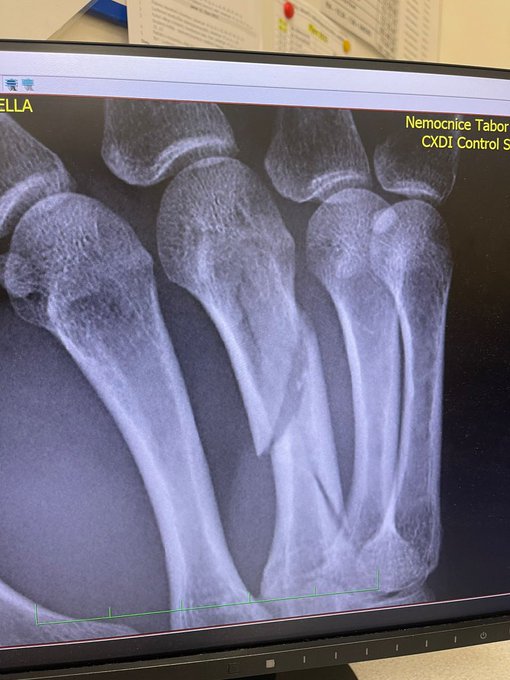

Brand se estrelló mientras realizaba un reconocimiento del recorrido checo el pasado sábado y se ha roto el hueso metacarpiano derecho. Esta fractura se encuentra en una zona sensible que los corredores necesitan tocar mucho durante las carreras y los entrenamientos de CX y la tendrá fuera de la competición por tiempo indefinido.